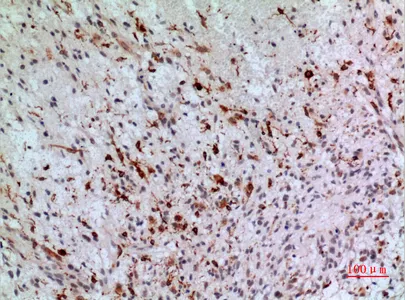

CEACAM1/5 Rabbit Polyclonal Antibody

Cat: APRab08615